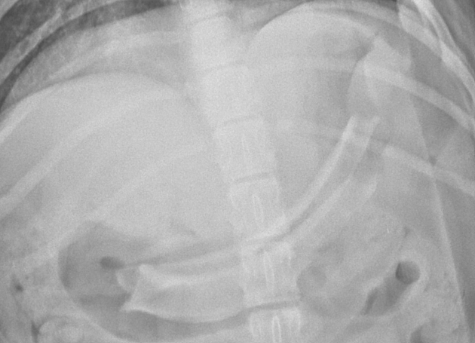

발작 환자 진료의 모든 것 : 진단부터 수술, 응급 관리까지

발작은 임상 현장에서 비교적 흔하게 접하지만, 원인 감별부터 치료 방향 결정까지 복합적인 판단이 요구되는 신경계 응급 질환입니다. 특히 발작의 원인이 다양한 만큼 정확한 감별진단과 단계별 치료 접근이 이루어지지 않을 경우 환자의 예후에 큰 영향을 미칠 수 있습니다.

본 웨비나에서는 발작 환자를 처음 접하는 단계부터 원인 감별, 약물 치료, 뇌종양 및 구조적 질환에 대한 수술적 접근, 그리고 응급중환자실에서의 발작 환자 관리까지 실제 임상 흐름에 맞춰 체계적으로 정리합니다.

• 발작 환자 접근 시 필수 감별진단 및 진단 프로토콜 • 발작 환자의 약물 치료 및 장기 관리 전략 • 뇌종양 및 구조적 질환에서의 외과적 치료 접근 • 응급 개두술 및 정밀 뇌종양 수술의 임상 적용 • 응급중환자실에서의 발작 환자 응급처치 방법 • 발작 환자의 입원 관리 및 모니터링 전략 • 실제 임상 증례 기반 진단 및 치료 의사결정 포인트 |